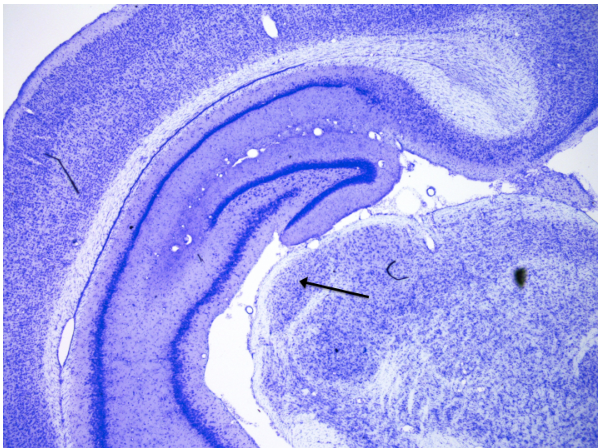

Hippocampus CA1

knowt flashcard image